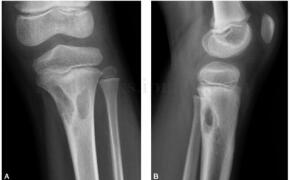

半个月前无明显诱因患儿自述走路时左侧膝部疼痛,左膝关节活动无明显影响。病来无发热、无盗汗。查体:患儿左胫骨近端无明显肿胀,无红肿,表面无破溃,无静脉怒张,局部无压痛,膝关节伸屈活动不受限(图3~5)。

图3 X线:左侧胫骨近侧干骺端可见多发囊状低密度影,周围可见硬化缘,邻近骨皮质略膨胀,周围软组织未见肿胀

图4 CT:左胫骨近端髓腔内及皮质内多发囊状骨质密度减低区,边缘见硬化缘,部分囊变区内见小结节状高密度影,左胫骨近端局部骨皮质缺损